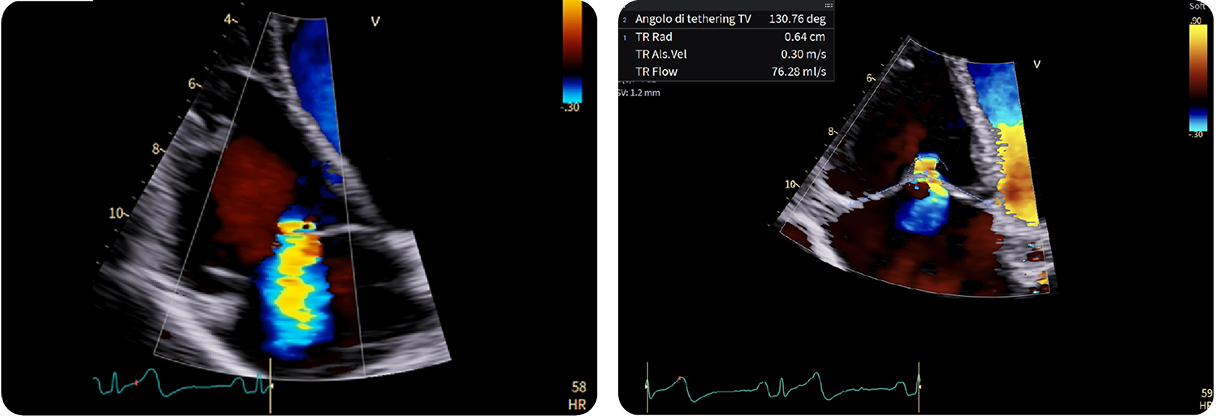

Fifty shades of grey

Caso condiviso da Marcello De Santis